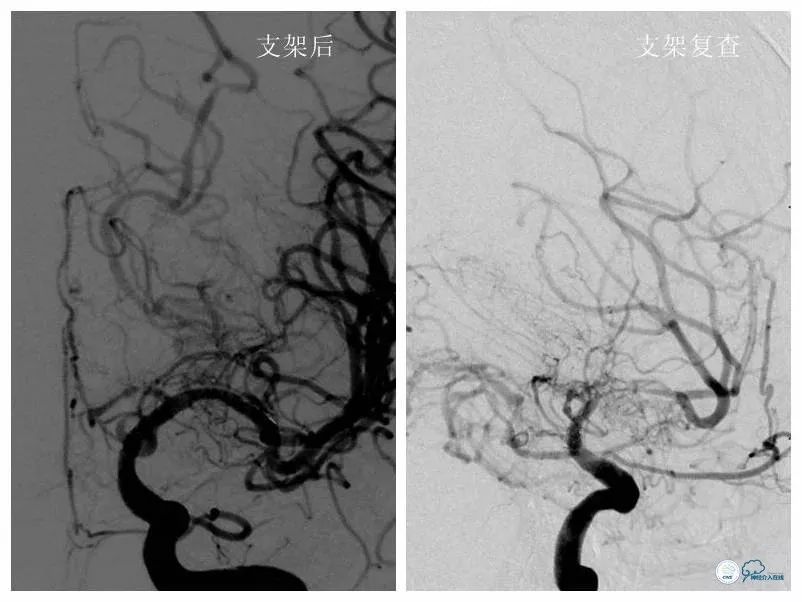

DSA(2018-4-12):左大脑中动脉支架术后再狭窄(图7)。

图7